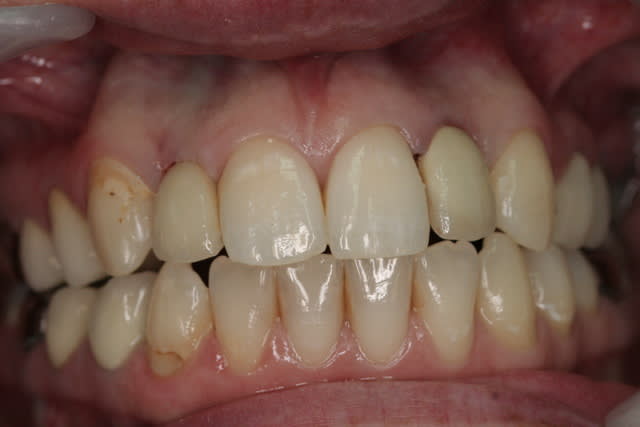

photos finish!!!

à noter...avec le flash...difficile de rendre le "naturel" de ces restaurations(teintes très claires)...après petite gingivoplastie pour harmoniser la hauteur des collets...(surtout pour 12...)